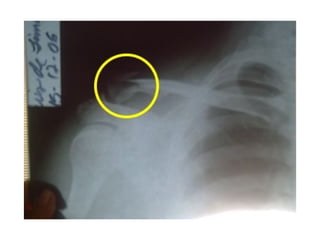

FRACTURAS DE LA CLAVICULA Las Fracturas de la clavícula son frecuentes, en el adulto por traumatismos aplicados en el hombro y en el recién nacido por tracciones efectuadas durante el parto.

FRACTURAS DE LA CLAVICULA Las relaciones que posee la clavícula con los vasos subclavios y nervios braquiales en su trayecto desde la base del cuello hacia la axila motivan que exista un  riesgo potencial de lesión vascular o nerviosa asociado a las fracturas claviculares.

FRACTURAS DE LACLAVICULA Las Fracturas de la clavícula son frecuentes, en el adulto por traumatismos aplicados en el hombro y en el recién nacido por tracciones efectuadas durante el parto.

FRACTURAS DE LACLAVICULA Las relaciones que posee la clavícula con los vasos subclavios y nervios braquiales en su trayecto desde la base del cuello hacia la axila motivan que exista un riesgo potencial de lesión vascular o nerviosa asociado a las fracturas claviculares.